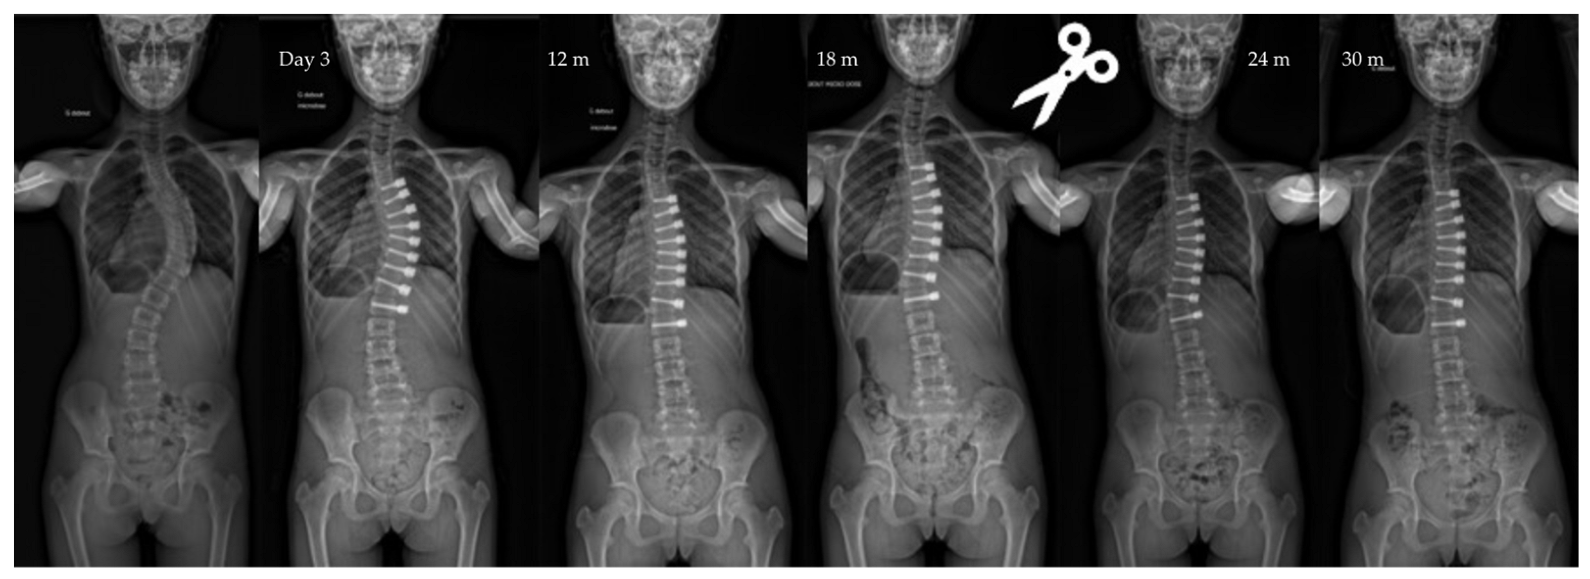

| Major curve | 49°(8,9°) | 27°(12°) | 22°(12°) | 19°(14°) | <0.01 |

| Overcorrection | 10 (11%) | 10 right thor. | 5 tether release | Between 1,5, and 2 y po |

| Cranial screw slippage | 6 (7%) | Thor. | - | 18 months po |